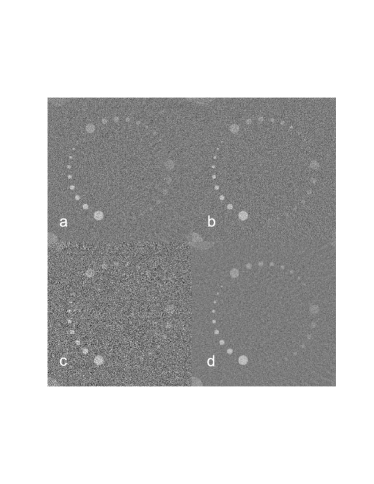

In order to evaluate we note that

| (25) |

Therefore, recalling Eqn. 14 and applying the chain rule,

| (26) |